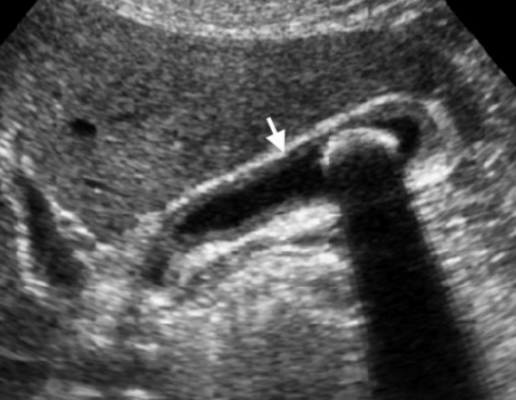

Острый калькулезный холецистит. После контрастного усиления визуализируется растянутый желчный пузырь (белые наконечники) со слегка утолщенной стенкой. Визуализируется камень в шейки желчного пузыря (белая стрелка).

Сверху изображения пациента 62 лет с калькулезным холециститом. На УЗИ визуализируется стенки желчного пузыря растянутые, с субсерозным отеком (указано белыми стрелками) и в просвете желчного пузыря камень и взвесь. На КТ визуализируется переход воспалительного процесса с желчного пузыря на соседние ткани (перихолецистит).

УЗИ и КТ желчного пузыря. Ксантогранулематозный холецистит. Слева на УЗИ визуализируется (помечено стрелками) утолщение стенки желчного пузыря с интрамуральным включением и с камнем в просвете органа. Справа на КТ выявляется утолщение стенки с гиподенсными включениями.

УЗИ (слева) и КТ (справа) желчного пузыря. На УЗИ ярко выраженное утолщение стенки желчного пузыря (указаны белыми стрелками). Множественные камни в просвете желчного пузыря (указано стрелкой). Компьютерная томография с контрастным усилением. На КТ визуализируются утолщение стенки с внутристеночными гиподенсными включениями. На КТ также выявлено, что процесс распространился на печень (указано стрелкой).